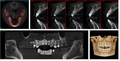

As a 3D rendition, CBCT offers an undistorted view of the dentition that can be used to accurately visualize both erupted and non-erupted teeth, tooth root orientation and anomalous structures that conventional 2D radiography cannot.[9]

Processing example using x-ray data from a tooth model: